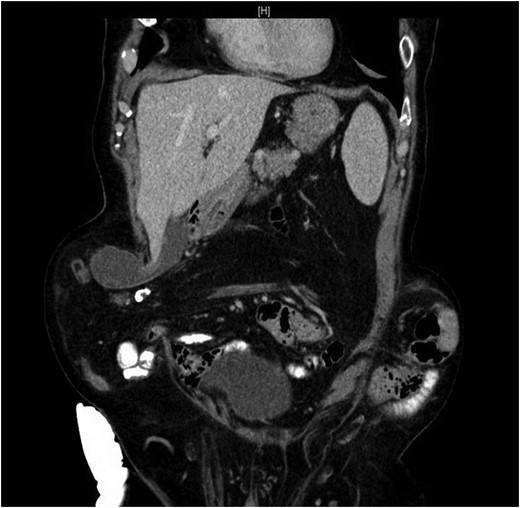

Our patient is an 89-year-old male with a history of a Hartmann’s procedure (2006) for Crohn’s disease of the sigmoid colon followed by a reversal of the colostomy with a diverting loop ileostomy (2008). Due to his comorbidities and age, the patient declined further surgery to reverse his loop ileostomy. Most recently, the patient presented to the emergency room with no ostomy output for the past 14 h, nausea and frequent burping. He reported a burning sensation around his ostomy. His physical examination revealed a large parastomal hernia in the right hemiabdomen and associated tenderness in the right upper quadrant, with no overlying skin changes. His white blood cell count was 8.1 (82.4% neutrophils), and he had normal liver function tests. A computed tomography (CT) scan of the abdomen and pelvis revealed a large parastomal hernia with a wide neck containing a distended gallbladder concerning for acute cholecystitis, as well as a small bowel obstruction with a transition point at the level of the hernia (Figs 1 and 2). A previous CT scan showed the same hernia with a nondistended gallbladder and non-obstructed bowel entering and exiting the stoma (Fig. 3).

Acute cholecystitis causing a small bowel obstruction within a parastomal hernia. Arrow points to transition point.